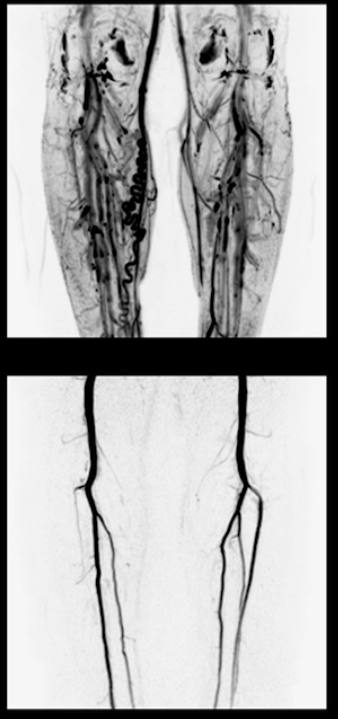

MRA нижніх кінцівок